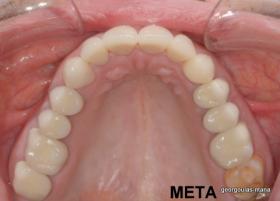

ΟΛΙΚΗ ΑΠΟΚΑΤΑΣΤΑΣΗ ΑΝΩ ΓΝΑΘΟΥ

Η ασθενής ήταν δυσαρεστημένη από την εμφάνιση των άνω δοντιών της. Ήθελε τα δόντια της να αποκτήσουν ομοιόμορφο, πιο λευκό χρώμα κ να αποκτήσει ένα πιο αρμονικό χαμόγελο με φυσική εμφάνιση. Λόγω των εκτεταμένων εμφράξεων σύνθετης ρητίνης στα πρόσθια δόντια, των εμφράξεων αμαλγάματος στα πίσω αριστερά δόντια αλλά και της υπάρχουσας γέφυρας στα πίσω δεξιά δόντια, και σε συνδυασμό με την επιθυμία της ασθενούς για φυσικό αποτέλεσμα αποφασίστηκε η τοποθέτηση ολοκεραμικών στεφανών στα δόντια της άνω γνάθου. Στη θέση του δεύτερου προγομφίου δεξιά τοποθετήθηκε εμφύτευμα. Πραγματοποιήθηκε περιοδοντική θεραπεία, ενδοδοντικές θεραπείες (απονευρώσεις) κ τοποθετήθηκαν ενδορριζικοί άξονες υαλονημάτων  όπου κρίθηκε απαραίτητο. Σε όλη τη διάρκεια της θεραπείας η ασθενής ήταν καλυμμένη αισθητικά κ λειτουργικά με προσωρινές αποκαταστάσεις.